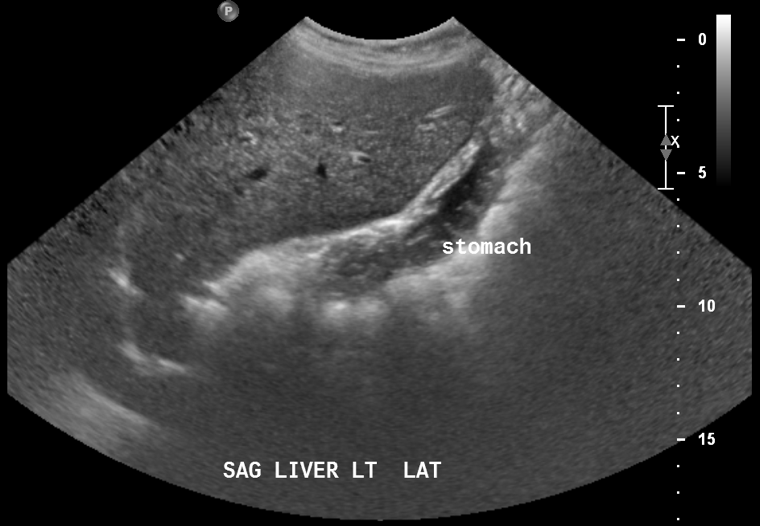

Diagnostic tests. Approximately 4 years ago, ultrasonography had exposed a heterogeneous hypoechoic lesion along the right lobe of the liver measuring 12 × 10 × 11 cm (Figure 1).

Figure 1. Ultrasonogram showing a mass in the right lobe of the liver.